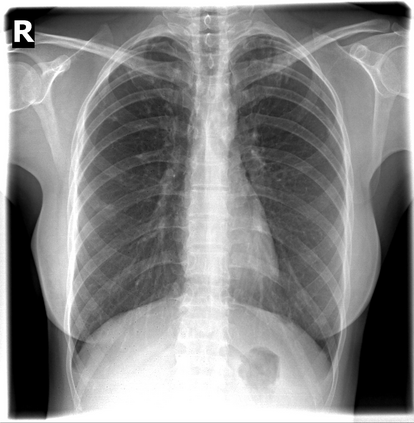

The evaluation of infectious disease processes on radiologic images is an important and challenging task in medical image analysis. Pulmonary infections can often be best imaged and evaluated through computed tomography (CT) scans, which are often not available in low-resource environments and difficult to obtain for critically ill patients. On the other hand, X-ray, a different type of imaging procedure, is inexpensive, often available at the bedside and more widely available, but offers a simpler, two dimensional image. We show that by relying on a model that learns to generate CT images from X-rays synthetically, we can improve the automatic disease classification accuracy and provide clinicians with a different look at the pulmonary disease process. Specifically, we investigate Tuberculosis (TB), a deadly bacterial infectious disease that predominantly affects the lungs, but also other organ systems. We show that relying on synthetically generated CT improves TB identification by 7.50% and distinguishes TB properties up to 12.16% better than the X-ray baseline.